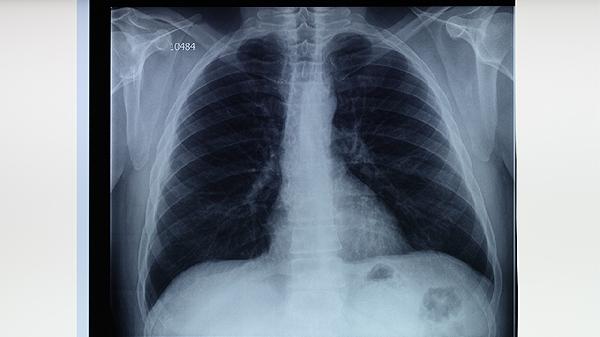

肺结核皮试后无需特殊护理,但应避免使用创可贴覆盖或涂抹药膏。日常注意观察注射部位变化,若出现直径超过15毫米的硬结、水疱或淋巴管炎,提示强阳性反应,需进一步进行胸部影像学检查。结核病确诊需结合临床症状、痰涂片检查和影像学结果综合判断,皮试仅作为筛查手段。